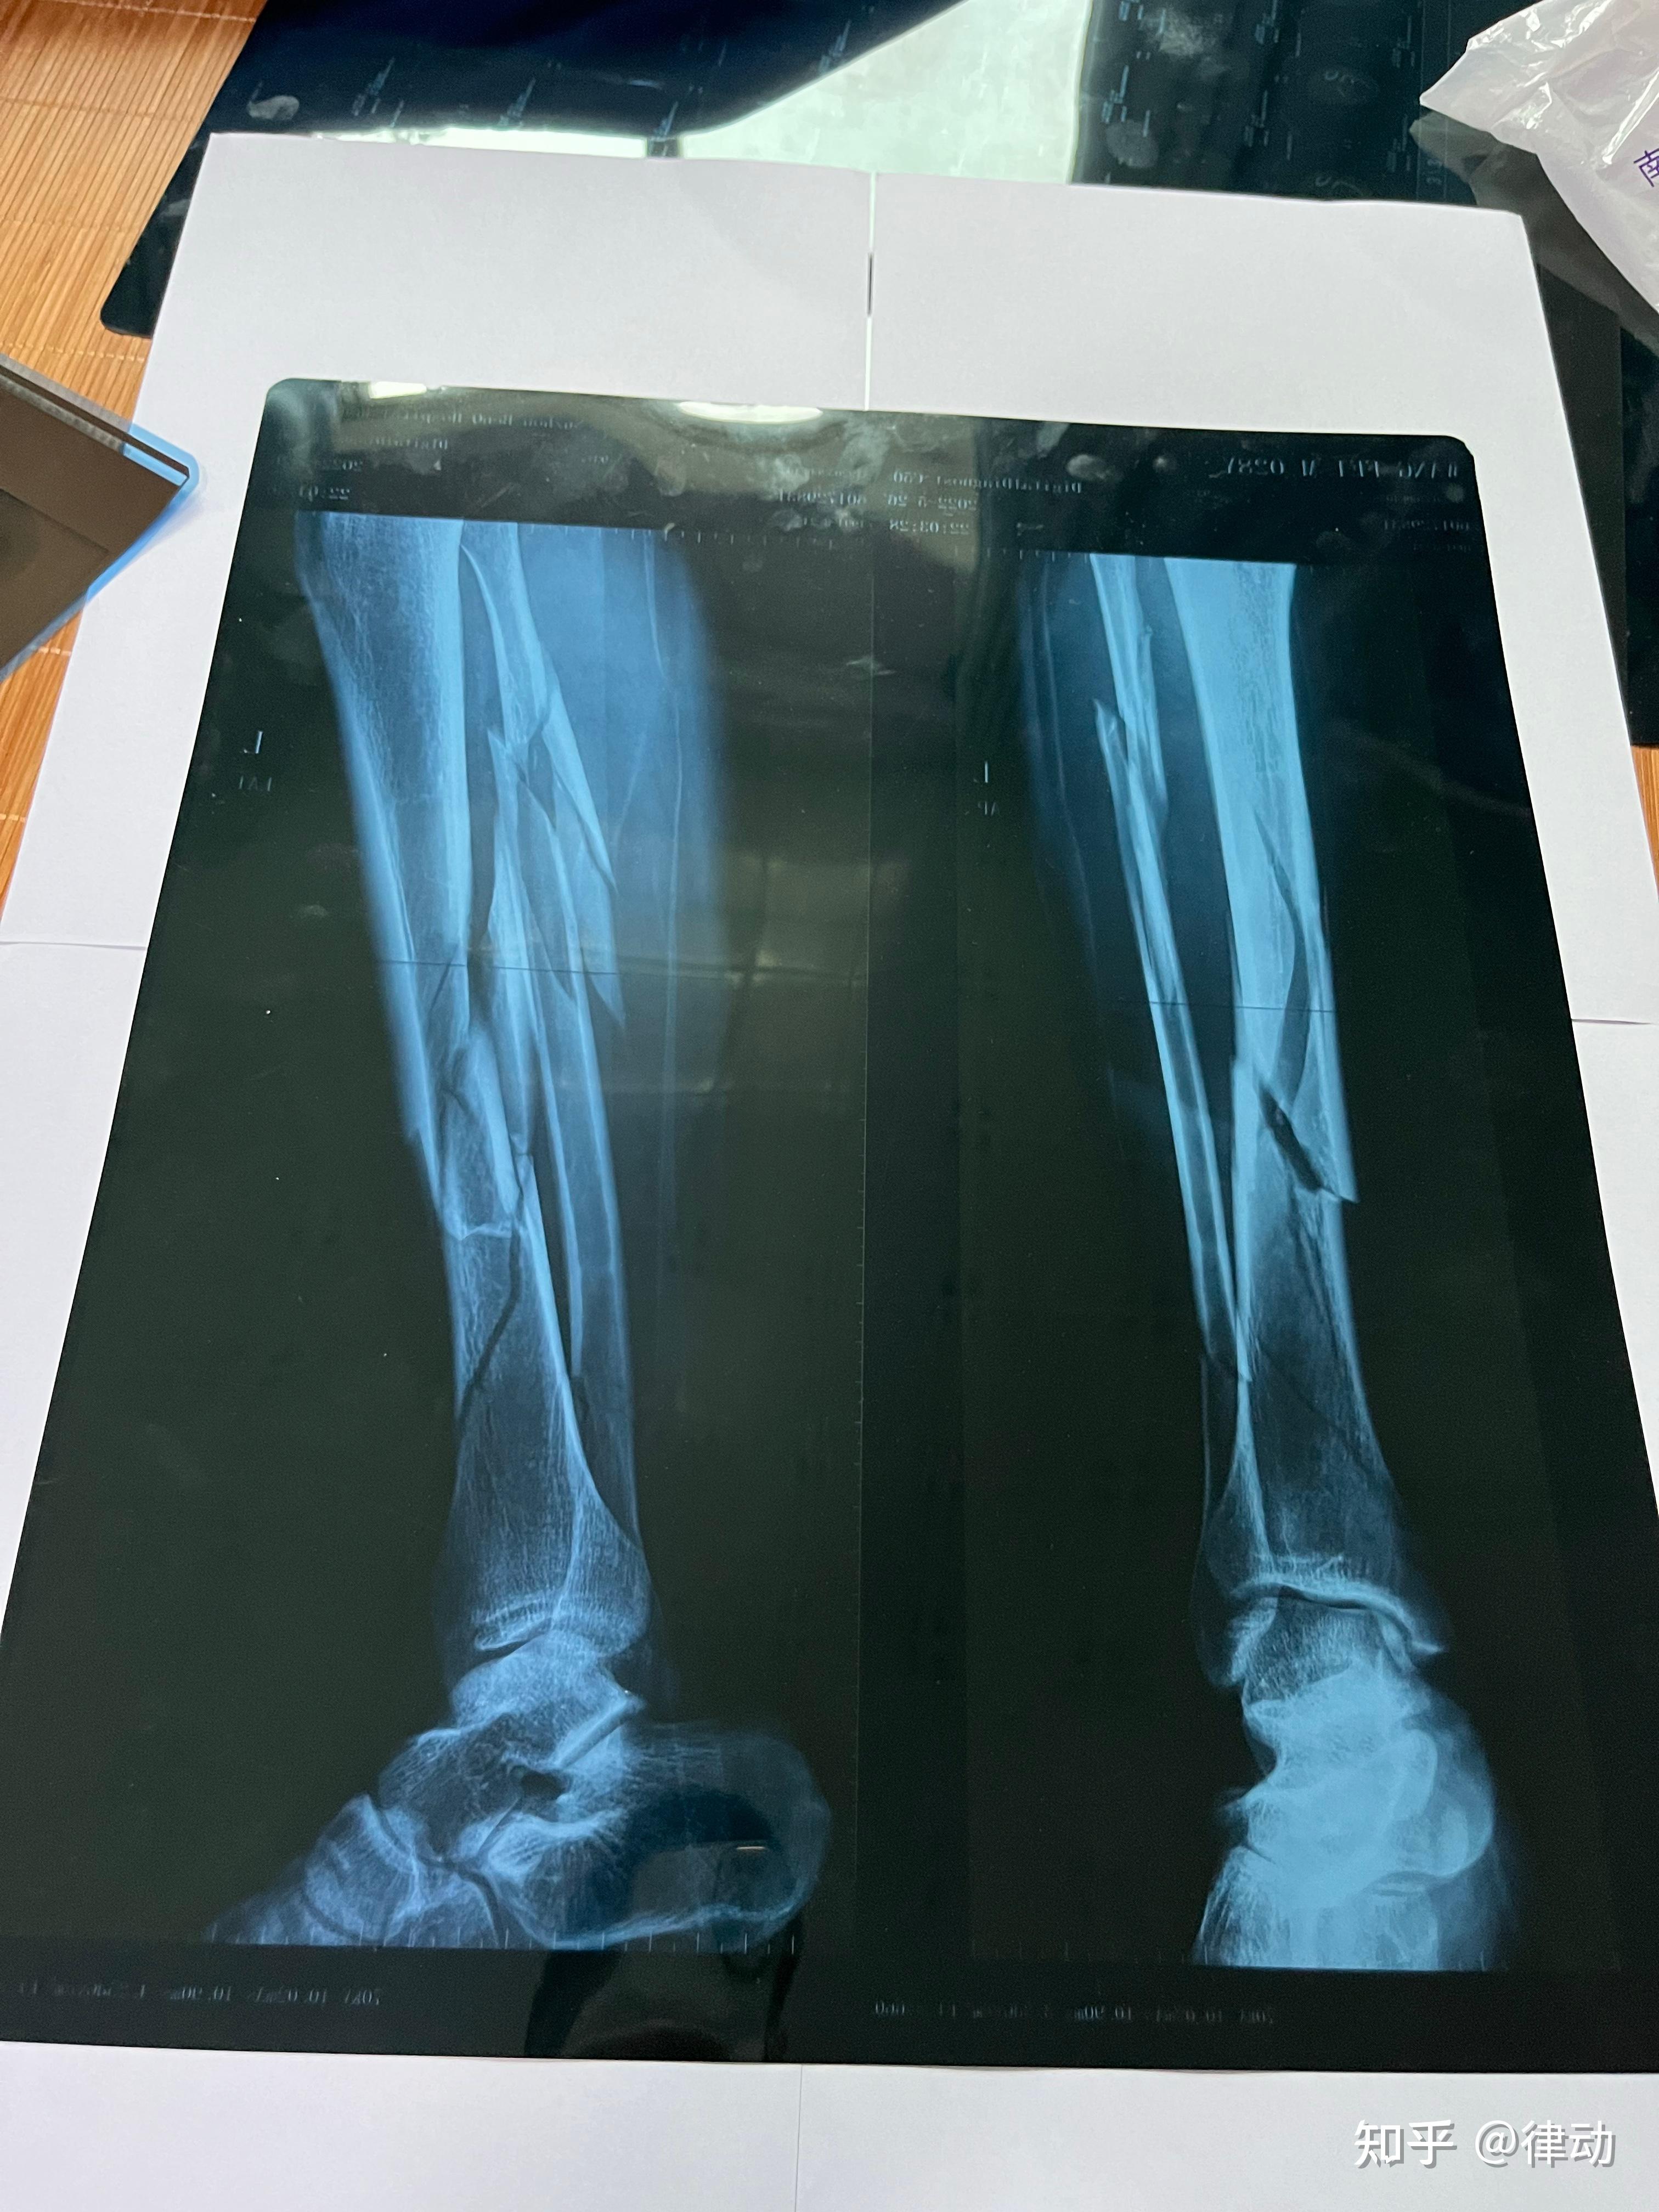

左小腿胫腓骨粉碎性骨折整个历程记录

小腿左胫腓骨中下段粉碎骨折,保守治疗.